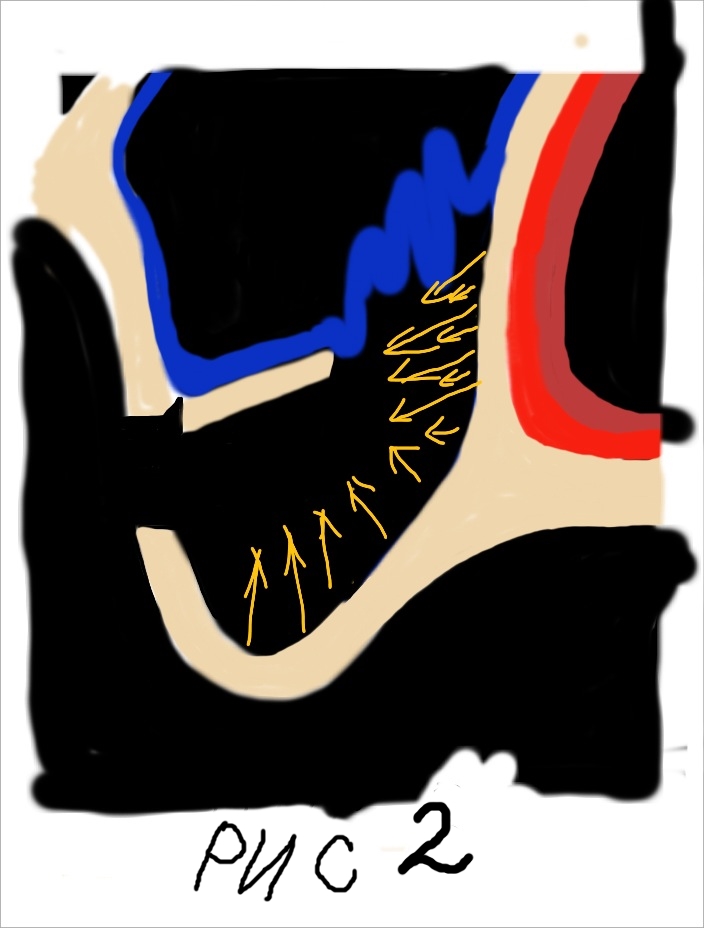

При этом, чем выше мы поднимаем слизистую пазухи тем больше кровоснабжения из соседних участков мы можем получить (рис 2).

При этом, чем выше мы поднимаем слизистую пазухи тем больше кровоснабжения из соседних участков мы можем получить (рис 2).  Сосудистая сеть наружной стенки носа многослойная и обильная. Следовательно, получить кровоснабжение из данного источника очень легко. Для этого необходимо как можно выше отсепарировать слизистую пазухи с носовой стенки. Благодаря этому мы получаем несколько плюсов. Во первых, напряжение слизистой уменьшается она становиться складчатой. Это предупреждает возникновение разрывов и трещин во время аугментации. Во вторых, мы получаем доступ к месту с обильным кровоснабжением которое крайне необходимо для последующего костеобразования и ремоделирования костной ткани.

Сосудистая сеть наружной стенки носа многослойная и обильная. Следовательно, получить кровоснабжение из данного источника очень легко. Для этого необходимо как можно выше отсепарировать слизистую пазухи с носовой стенки. Благодаря этому мы получаем несколько плюсов. Во первых, напряжение слизистой уменьшается она становиться складчатой. Это предупреждает возникновение разрывов и трещин во время аугментации. Во вторых, мы получаем доступ к месту с обильным кровоснабжением которое крайне необходимо для последующего костеобразования и ремоделирования костной ткани.